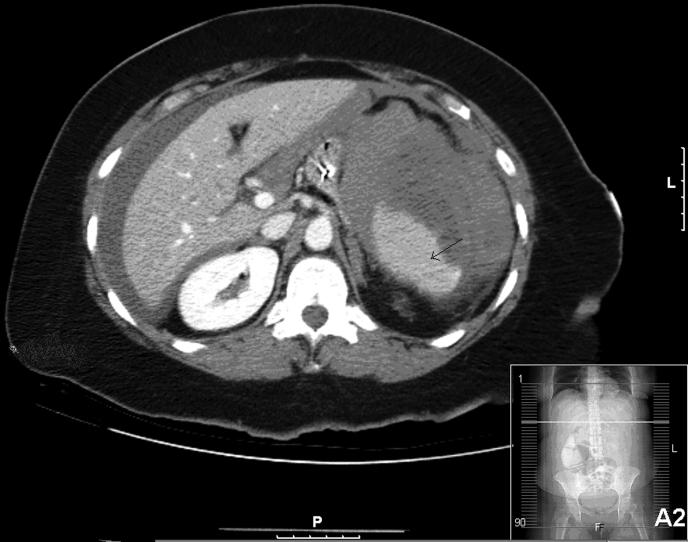

Splenic injury is a rare but serious complication of colonoscopy. Since the mid-1970s, 68 splenic injuries during colonoscopy including our 2 cases have been described. With the increasing use of colonoscopy, endoscopists, surgeons, and radiologists are more likely to encounter this unusual complication. Any cause of increased splenocolic adhesions, splenomegaly, or underlying splenic disease might be a predisposing factor for splenic injury during colonoscopy. However, it can occur in patients without significant adhesions or underlying splenic pathology. The diagnosis is often described in the literature as delayed, because many physicians are not aware of this complication of colonoscopy. Although computerized tomography is highly sensitive, knowledge of this complication is the best tool to aid in early diagnosis. Patients with abdominal pain, hypotension, and a drop in hematocrit without rectal bleeding after colonoscopy should be suspected of having splenic injury. Early recognition and interdisciplinary management are required to assure successful management of this potentially life-threatening injury. Patients with hemodynamic instability most often undergo surgery. We present 2 cases of splenic injury secondary to colonoscopy that required splenectomy.

脾损伤是结肠镜检查中一种罕见但严重的并发症。自20世纪70年代中期以来,包括我们的2例病例在内,已有68例结肠镜检查期间发生脾损伤的病例被报道。随着结肠镜检查的使用日益增加,内镜医师、外科医生和放射科医生更有可能遇到这种不寻常的并发症。脾结肠粘连增加、脾肿大或潜在的脾脏疾病的任何原因都可能是结肠镜检查期间脾损伤的诱发因素。然而,它也可能发生在没有明显粘连或潜在脾脏病变的患者中。文献中常称诊断会延迟,因为许多医生并不知晓结肠镜检查的这种并发症。尽管计算机断层扫描高度敏感,但了解这种并发症是有助于早期诊断的最佳工具。结肠镜检查后出现腹痛、低血压和血细胞比容下降且无直肠出血的患者应怀疑有脾损伤。需要早期识别和多学科管理,以确保成功处理这种潜在的危及生命的损伤。血流动力学不稳定的患者大多需要接受手术。我们报告2例结肠镜检查继发脾损伤并需要行脾切除术的病例。